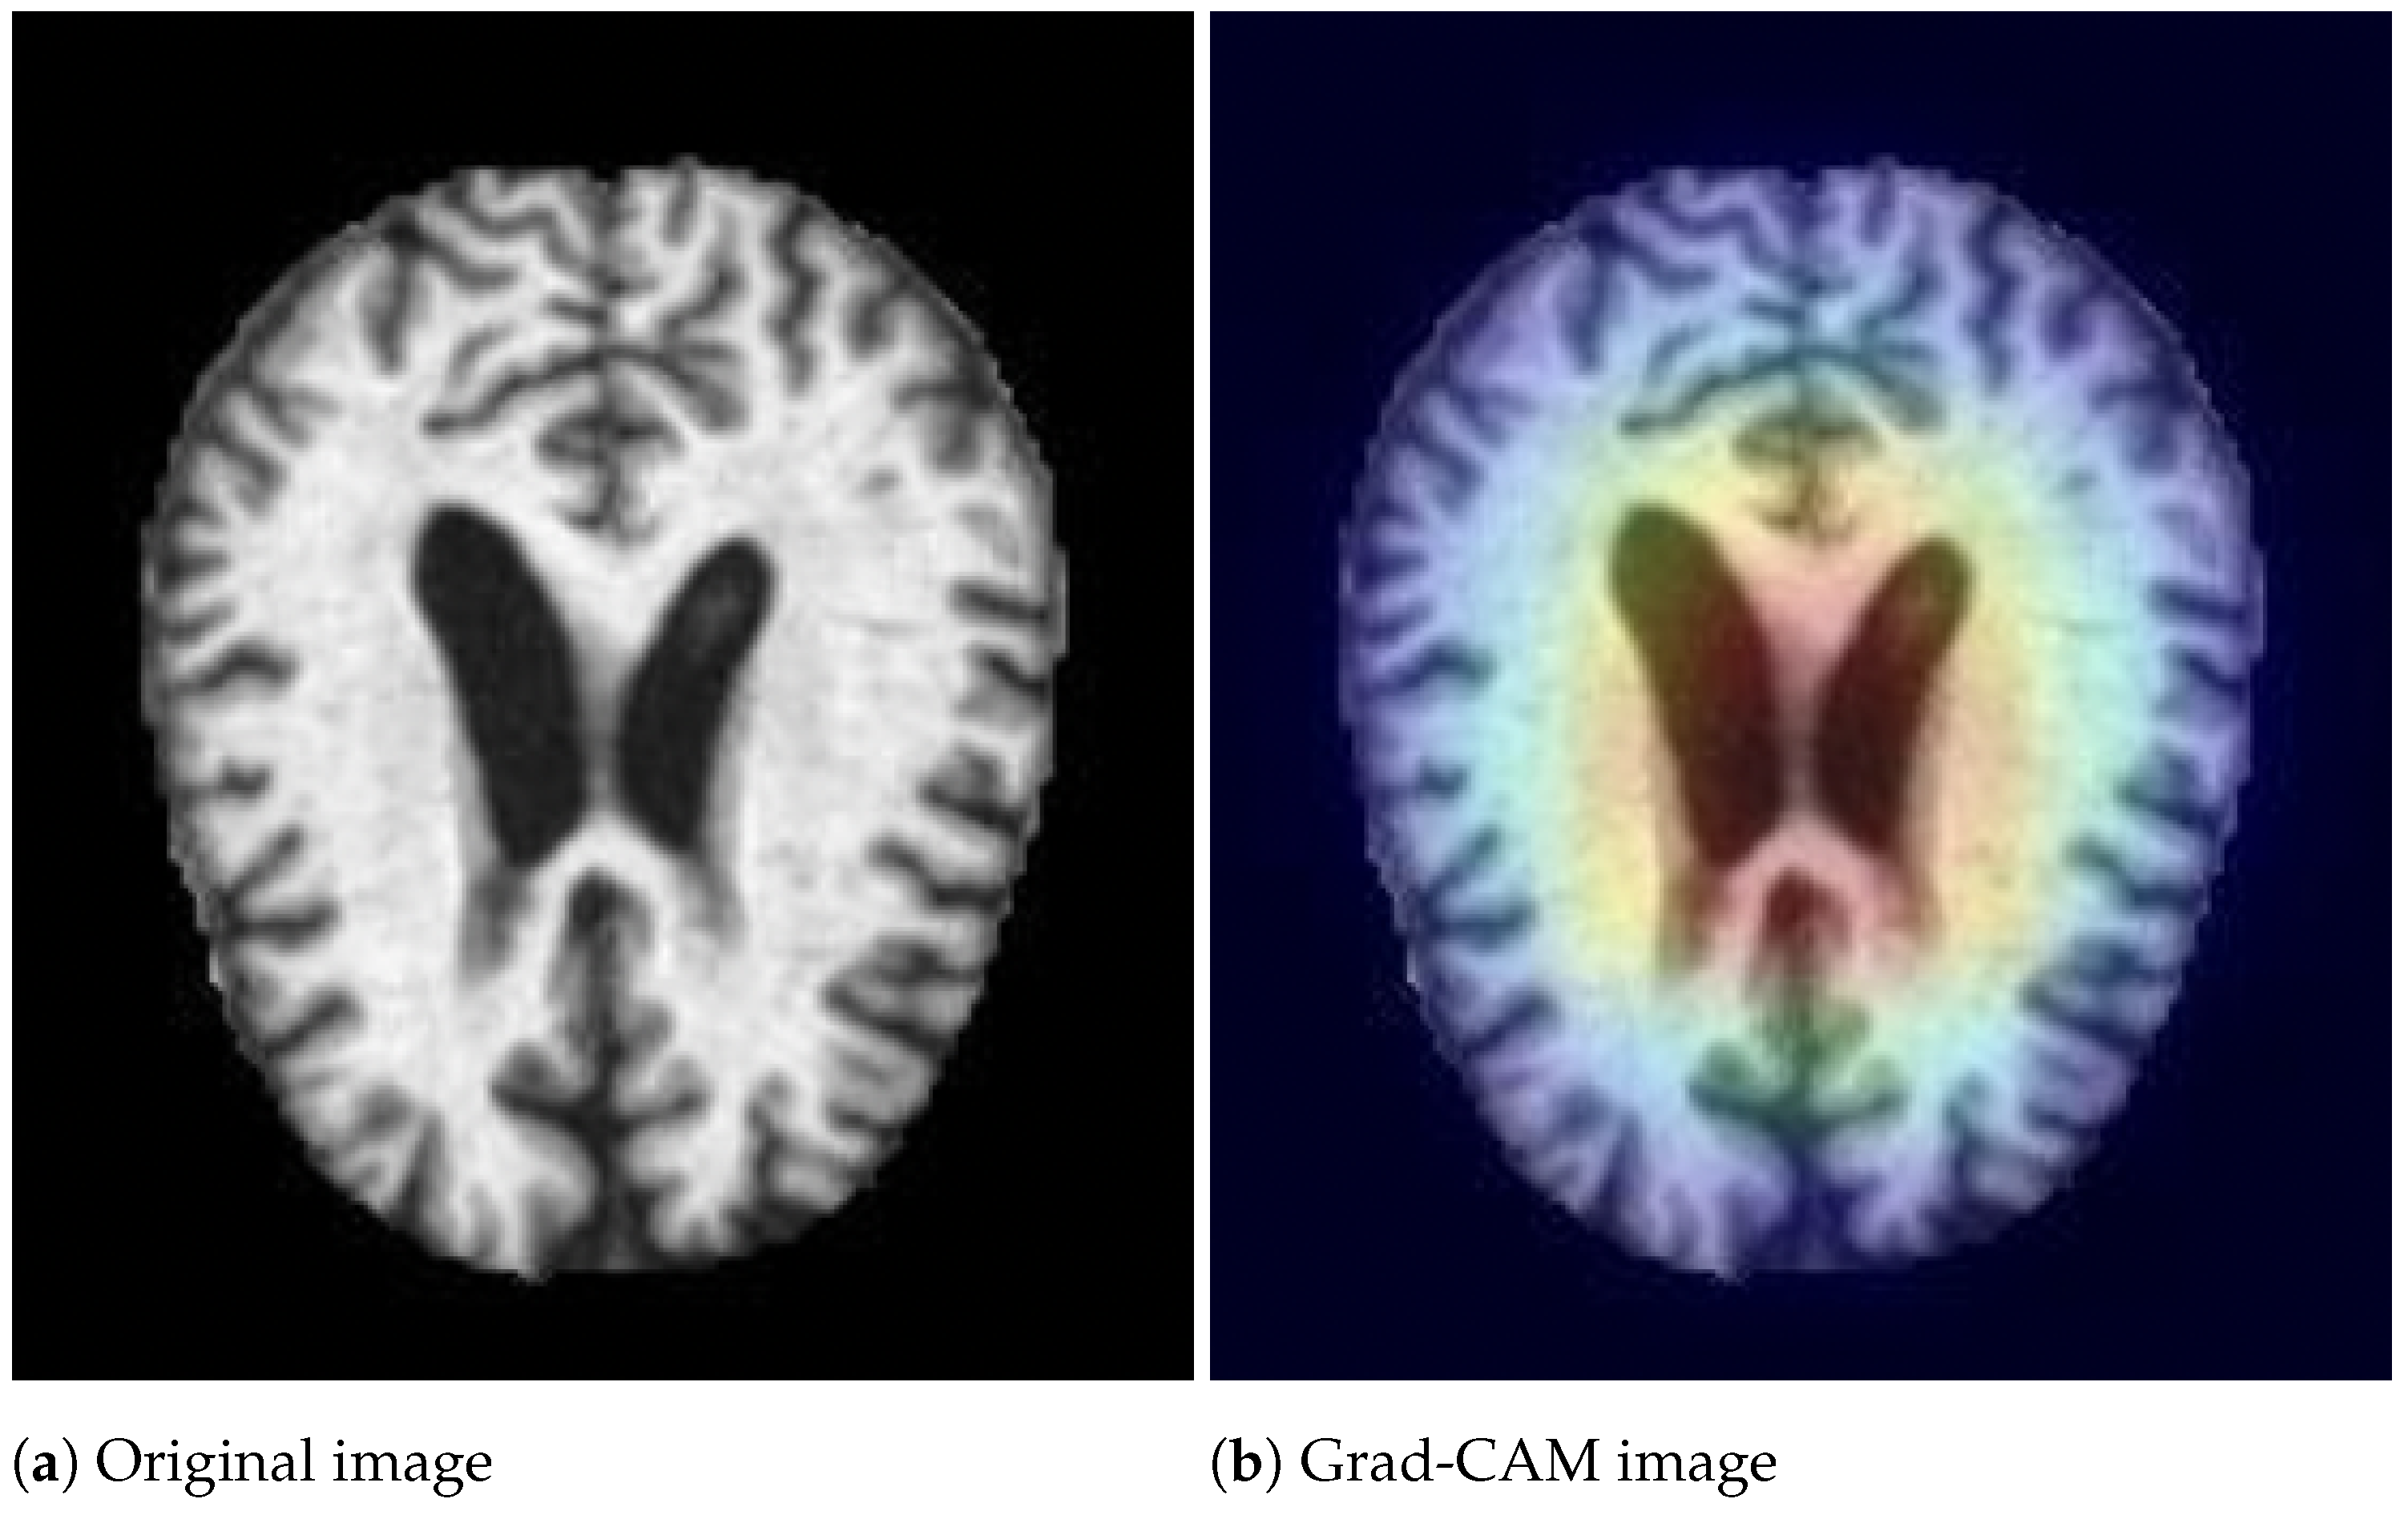

- Selvaraju, R.; Cogswell, M.; Das, A.; Vedantam, R.; Parikh, D.; Batra, D. Grad-cam: Visual explanations from deep networks via gradient-based localization. In Proceedings of the IEEE International Conference On Computer Vision, Venice, Italy, 22–29 October 2017; pp. 618–626. [Google Scholar]